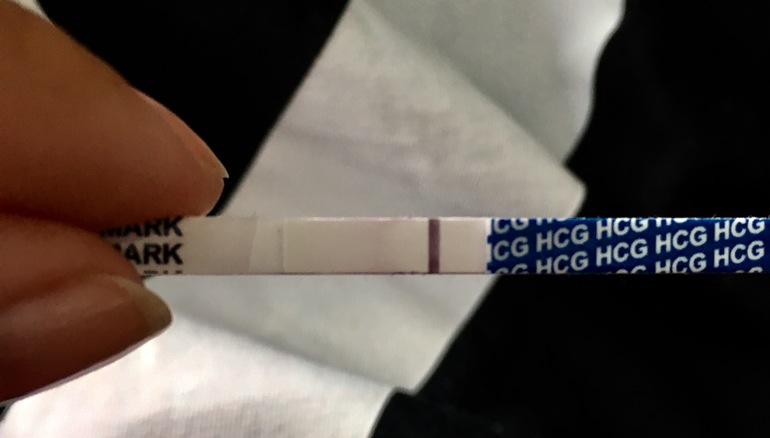

Видно ли полосочку🤷🏻♀️🙏🏻 Так хочется 😇

Добрый день!☺️ Сижу в этом сообществе давно, даже когда ещё не начали планировать было просто интересно читать) Больше всего нравится, как все друг друга поддерживают и понимают. Увы в реальной жизни не все могут понять почему ты так часто делаешь тесты и так внимательно в них всматриваешься🙄🤷🏻♀️ Тут к счастью я не одна такая , поэтому со спокойной душой делюсь своим утренним тестом 🙄 Раньше такого не было,я в замешательстве от этой мутной полосочки🙈 И радоваться страшно и верить в хорошее хочется. Цикл сейчас нестабильный, предположительно +- 6 ДПО. Появилась она ещё до высыхания в первые 10 минут, го сфоткала только сейчас😒 Буду благодарна за ваше мнение)

Больше на реагент похоже. Полосочка тонкая... но лучше переделать конечно завтра. Удачи, может завтра увидим привет от бурундучка

Извините, мне кажется полоска не там где надо. У меня был такой реагент  Мне писали, что не бер, но я очень надеялась.

реагент, не в том месте,еще и расплылся как пятно

на 6 дпо только реагенты в ЛЮБОМ случае можно увидеть ,даже если б.., тест должен быть с высокой чувствительностью раз так рааано делаете.

Я обычно все вижу)

Но чет пока пусто(

Смазано, но хорошо видно, все-таки там четкая вторая.

Какой-то странный тест, ну и рано очень делаете.

Полосочки не видно, но если правда 6 ДПО то и рано для неё. Малышастрик может ещё и не прикрепился и ХГЧ соответственно не растёт пока. Но все возможно!!! Так что подождите ещё и сделайте ещё!

Нене,это не то. Полоска не там,да и на 6 дпо вам это тест еще не покажет.

Что-то есть, надо переделать)

Пусто. Там где надо полоски нет.

Я не вижу(